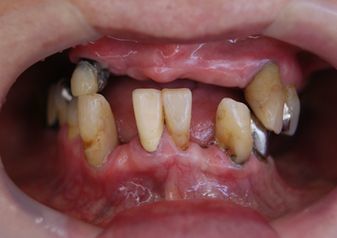

下顎fullインプラント

下顎のフルインプラントです。6本のインプラント(4本では不安です)を埋入して上部構造はスクリュウで固定してます。下の総義歯はみなさんどうしても浮き上がってきて食べにくいです。インプラントを埋入して即時負荷をかけるのはどうかと思いますが、骨と結合した後ならかなり頑丈な上部構造ができて、硬いものでも噛みやすくなります。

●● 様 男性 70代

治療の期間・回数:6か月、10回

治療の価格:150万円/下顎

治療のリスクや副作用:手術後に、痛みや腫れ、出血、合併症などを引き起こす可能性があります。噛む感覚がご自身の歯と異なる場合があります見た目がご自身の歯と異なる場合があります。手術後にメインテナンスを継続しないと抜け落ちる可能性があります。